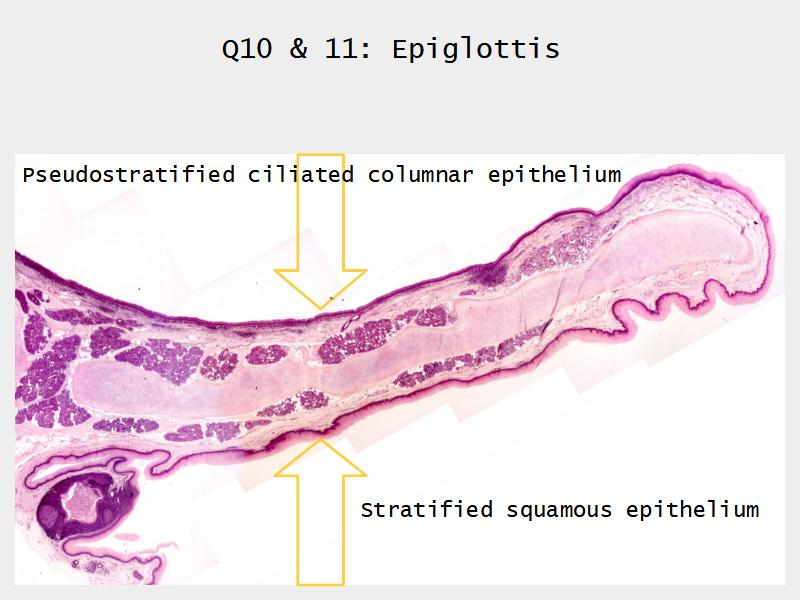

Epiglottis

Respiratory epithelium

- Pseudostratified

- Ciliated

- Columnar

- Epithelium with

- 4 Cells

- Ciliated columnar cells

- Non-ciliated columnar cells

- Goblet cells

- Basal cells